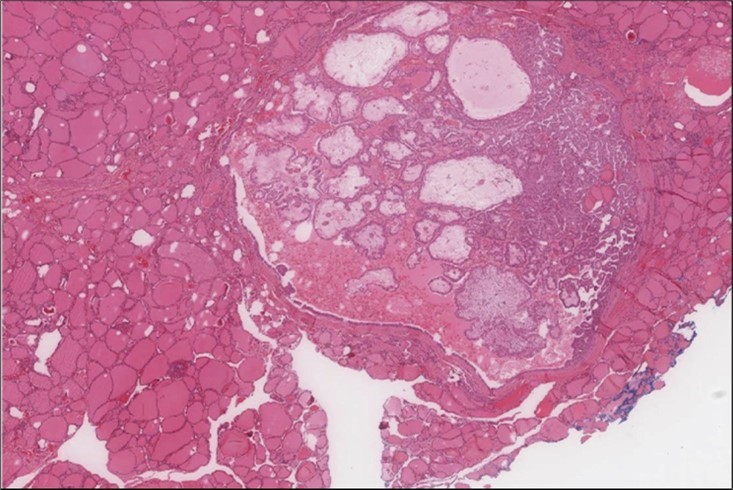

Figure 5.Liver biopsy Lower power of the liver core showing normal liver and part of the metastatic foci (H&E, x4)

Figure 6.Liver Biopsy Higher power showing the metastatic foci is almost identical to what is seen in the thyroid with the highly atypical spindle cells. (H&E, ×200).

cancer, or other metastatic tumors without further testing with genetic or molecular studies 3, 7. Immunohistochemical testing plays a vital role in differentiating LMS from such similar tumors as it stains positive for vimentin and smooth muscle actin (SMA), and is variably positive for HHF35, desmin (50%-100%), and H-caldesmon 3, 6. Moreover, there were no reported cases where thyroid LMS stained positive for thyroglobulin, cytokeratin, calcitonin, chromogranin, or protein S100 3. Our patient’s left thyroid biopsy showed the characteristic microscopic features and was positive for SMA, desmin, caldesmon, P63 with patchy EMA (Figure 1, Figure 2, Figure 3, Figure 4) as well as her liver biopsy (Figure 5, Figure 6, Figure 7); whereas her right thyroid showed clear papillary thyroid cancer cell features (Figure 8, Figure 9).